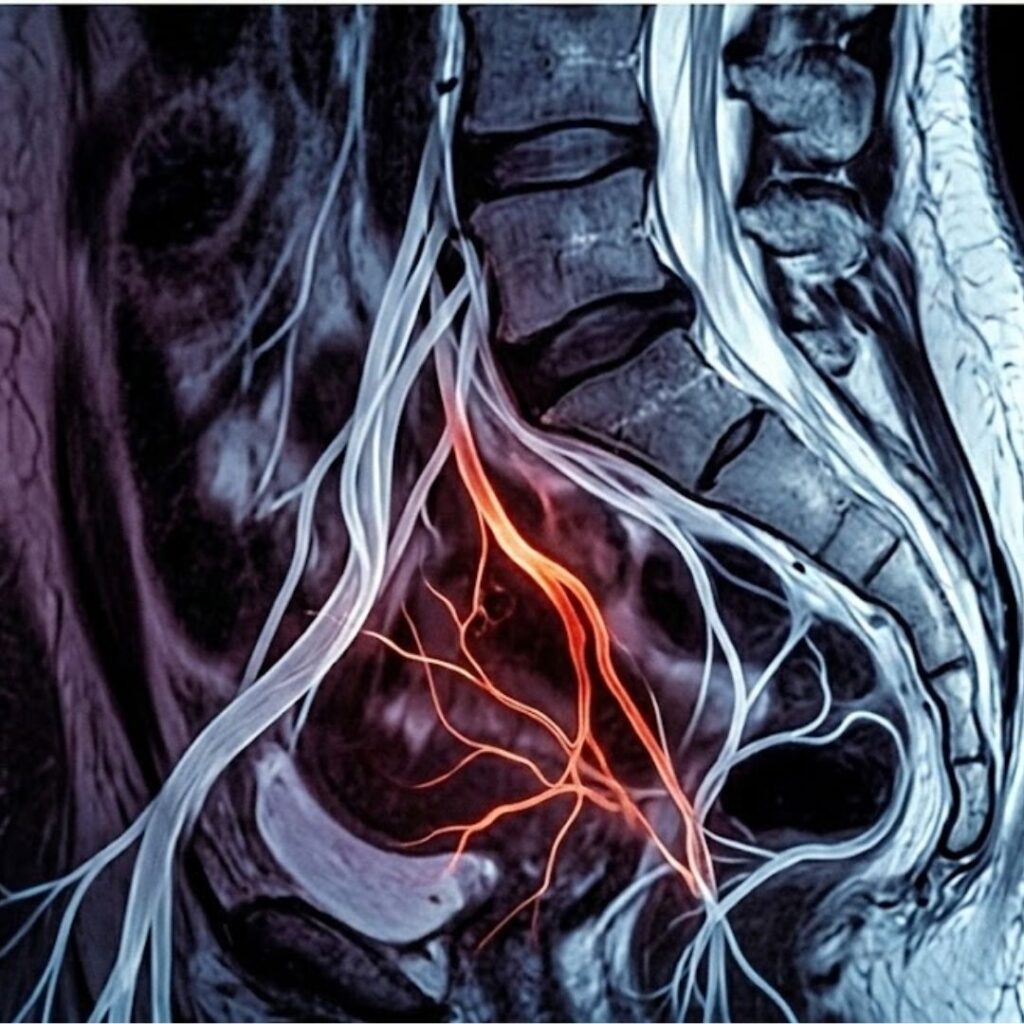

What Happens When the Wiring Degrades

Think of a copper cable running between a light switch on one side of a room and a lamp on the other.

When the cable is intact and its insulation is healthy, you flick the switch and the lamp lights immediately.

The signal travels cleanly, at full strength, with no loss.

Now imagine that the insulating layer around the cable has been slowly, invisibly degrading for fifteen or twenty years.

Not snapped.

Not visibly broken.

But the protective coating has been wearing away — millimetre by millimetre, year by year — until the copper inside is exposed in places, and the signal that travels along it begins to lose coherence.

One day you flick the switch and the lamp flickers.

Then it takes a moment to come on.

Then it comes on dimly.

Then there are days when it doesn’t come on at all.

The switch is fine.

The lamp is fine.

The problem is in the cable.

This is also why medication becomes progressively less effective for so many men over time.

Drugs like sildenafil and tadalafil work by amplifying the vascular response — they force the blood vessels to dilate more aggressively, compensating for the weakened nerve signal.

For a while, this works. But as the nerve pathway continues to degrade, even the pharmacologically amplified response can no longer compensate.

The doses stop being effective. The windows of effectiveness shorten.

You are not failing the medication.

The medication was never treating your actual problem.

The only genuine solution for progressive cavernous nerve demyelination is to address the nerve pathway itself — to restore the wiring, not to turn up the volume at the lamp end of a fraying cable.